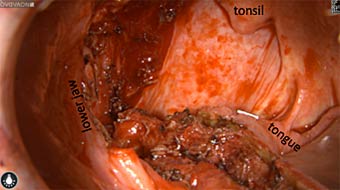

Intraoperative imaging panitumumab-IRDye800 (fluorescence)

Primary tumor prior to resection

Wound bed post re-resection of tumor

Fluorescence imaging of the tumor was performed prior to resection and after resection to “check” the wound bed. In the upper row the tumor is clearly visible with fluorescence and in the bottom row you can see that the wound bed is empty – there is no suspicious fluorescence left. The middle column of tiles show the fluorescence signal in black and white where the “white” represents the tumor and the black the background (= no fluorescence signal). The right column of tiles shows the overlay of the brightfield photo (in greyscale) and the fluorescence (red-yellow-blue heatmap). This image provides anatomical context to the surgeon – the surgeon can see where is the fluorescence located with regard to the tumor area.